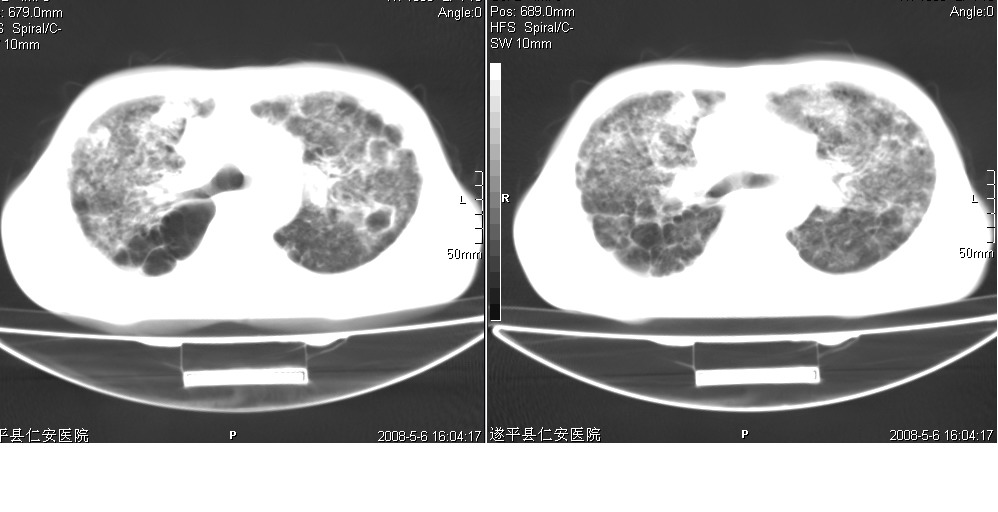

以下是引用光线在2008-5-6 18:36:00的发言:[br]双肺结核(左上肺空洞形成)、间质性改变合并感染,右肺大泡;右侧胸膜增厚。

以下是引用zsl6918在2008-5-7 1:54:00的发言:[br]首先肺泡蛋白质沉着症,其次考虑机遇性感染。